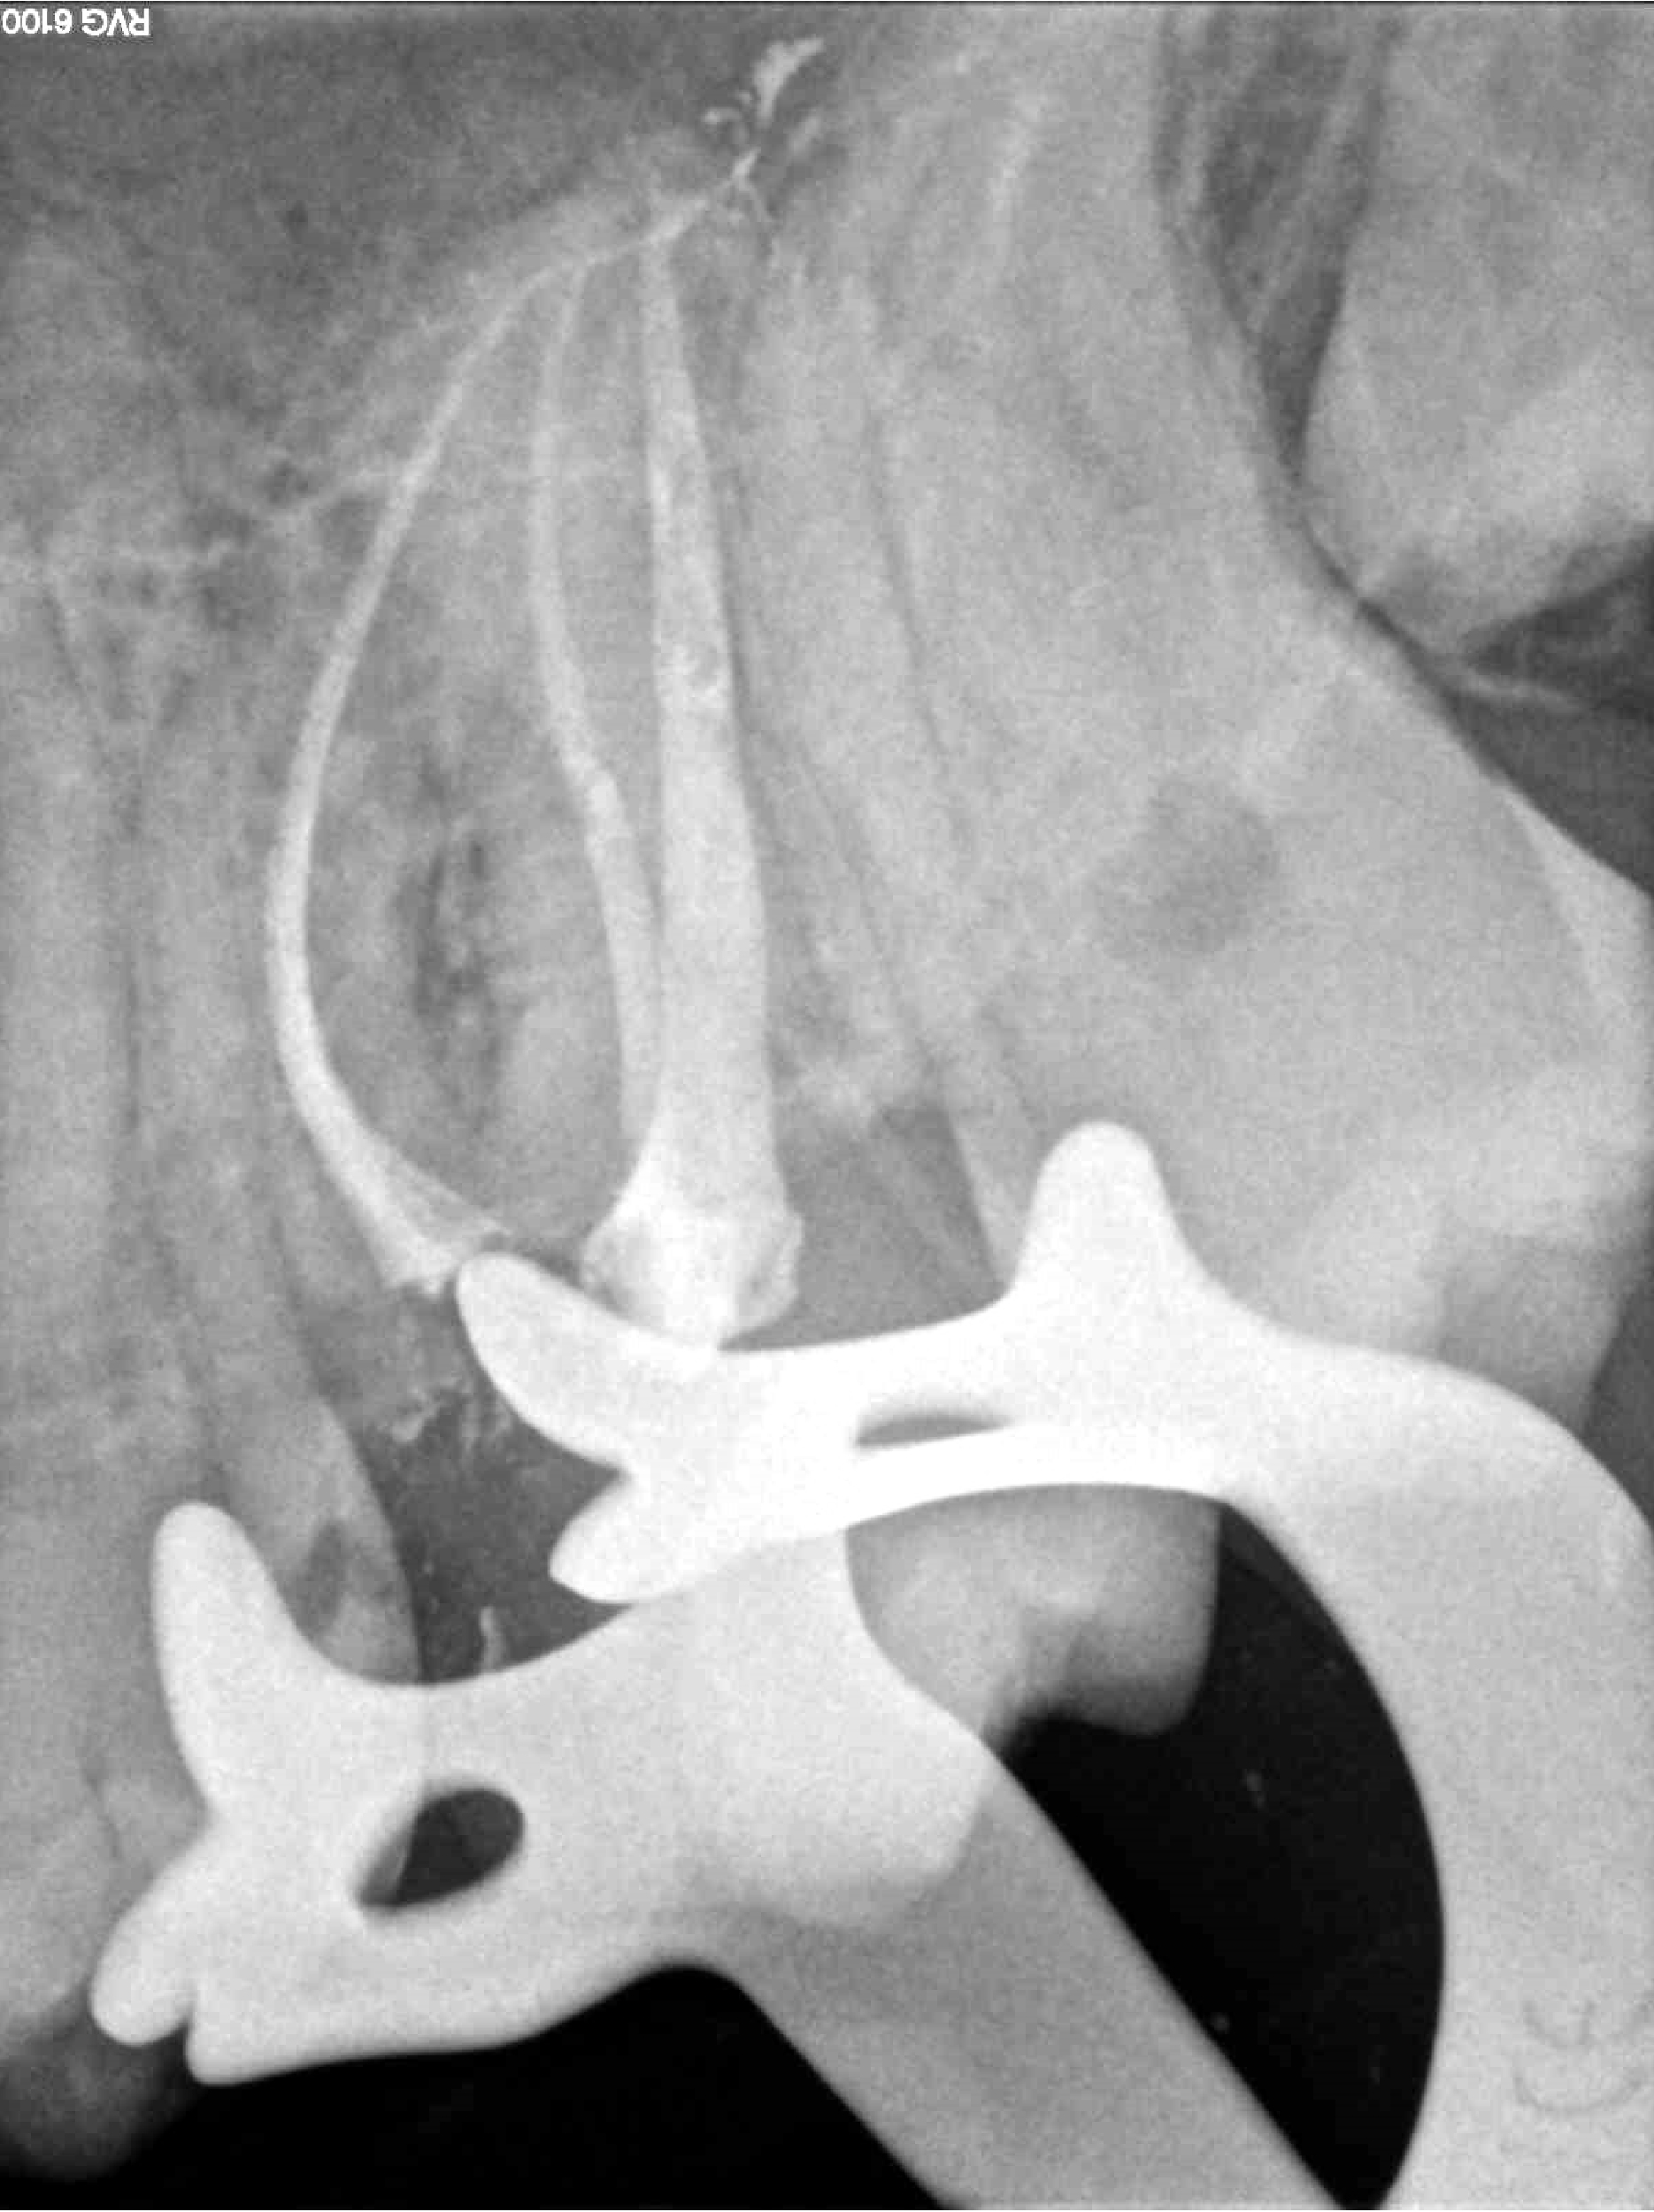

Principalmente me dedico a intentar salvar dientes a través de tratamientos endodónticos, todo tipo de intervenciones quirúrgicas relacionadas con la endodoncia: microcirugía apical, sellado quirúrgico de reabsorciones, amputaciones radiculares y últimamente autotrasplantes, reimplantes, extrusiones quirúrgicas parciales, todo esto con un enfoque mínimamente invasivo.

Soy perfeccionista y cuidadosa con los detalles, intento abordar los casos de una forma lo más conservadora posible con la estructura dental, aunque lleve más tiempo y sea más complejo desde el punto de vista técnico.

Últimos trabajos de especial complejidad relacionados con tratamientos de endodoncia, traumatología dental y microcirugía apical.